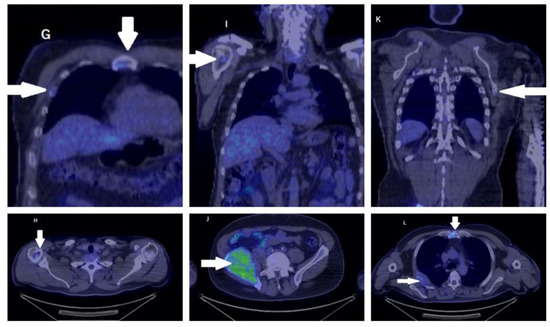

2. Case Report